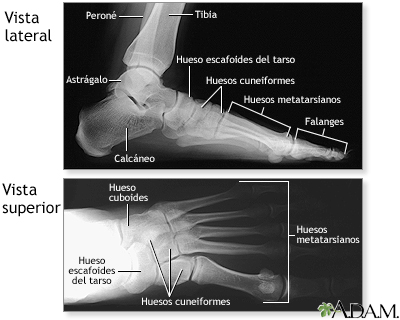

Radiografía del pie normal

Junto con las preguntas de la historia clínica, es posible que el médico necesite tomar radiografías de los pies que ayuden en la elaboración de un diagnóstico con el fin de determinar la causa del dolor de pie. En caso de que el pie esté fracturado, se le colocará un yeso y los dedos fracturados se aseguran con una cinta .